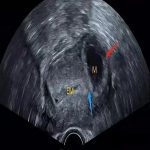

她在被确诊为宫外孕后,大理的医院只能切除她的输卵管,她果断从大理来到北京,安太医院再一次救助了她。

治疗宫外孕,安太医院3D腹腔镜下开窗取胚找病因,宫外孕宫内转移是安太医院继宫外孕开窗取胚后再次创新的技术。安太创新,永远止境!